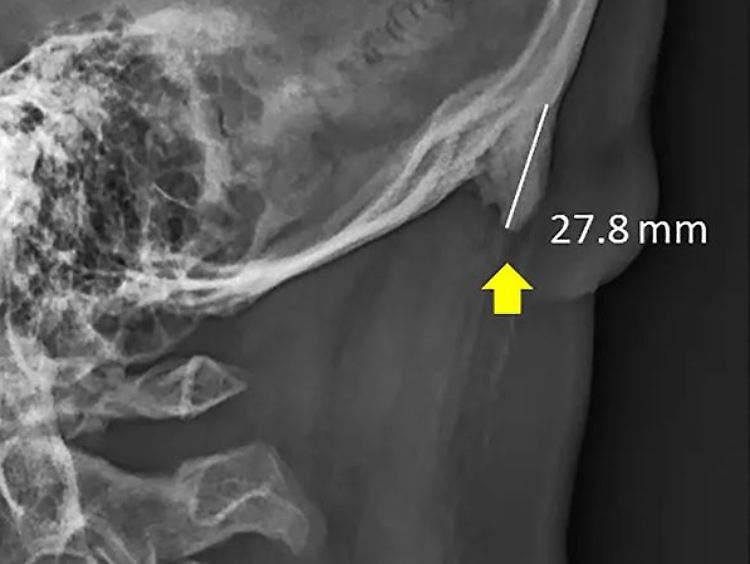

Das Röntgenbild zeigt die Exostose eines 28-Jährigen.

(Foto: David Shahar, University of Sunshine Coast, Queensland)

Die Forscher hatten über einen Zeitraum von drei Jahren insgesamt 1200 Röntgenaufnahmen des Schädels und der Halswirbelsäule von Patienten im Alter zwischen 18 und 86 Jahren ausgewertet. Dabei stellten sie bereits 2016 fest, dass die erkennbaren knöchernen Veränderungen am Hinterkopf vor allem bei jungen Männern im Alter von 18 bis 30 Jahren zu sehen waren. Insgesamt stellten die Forscher ein Knochenwachstum von drei bis fünf Millimetern bei rund 40 Prozent der untersuchten Personen fest. In extremen Fällen konnten sogar zehn Millimeter und mehr gemessen werden. Normalerweise treten solche Veränderungen nur im hohen Alter bei Menschen auf, die sich über Jahre hinweg starken körperlichen Belastungen aussetzen.